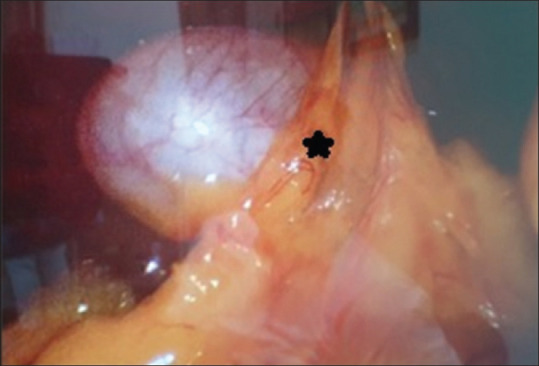

图 8

胆囊体部和颈部粘连网膜的术中图像(包含图片、插图等的外部文件。